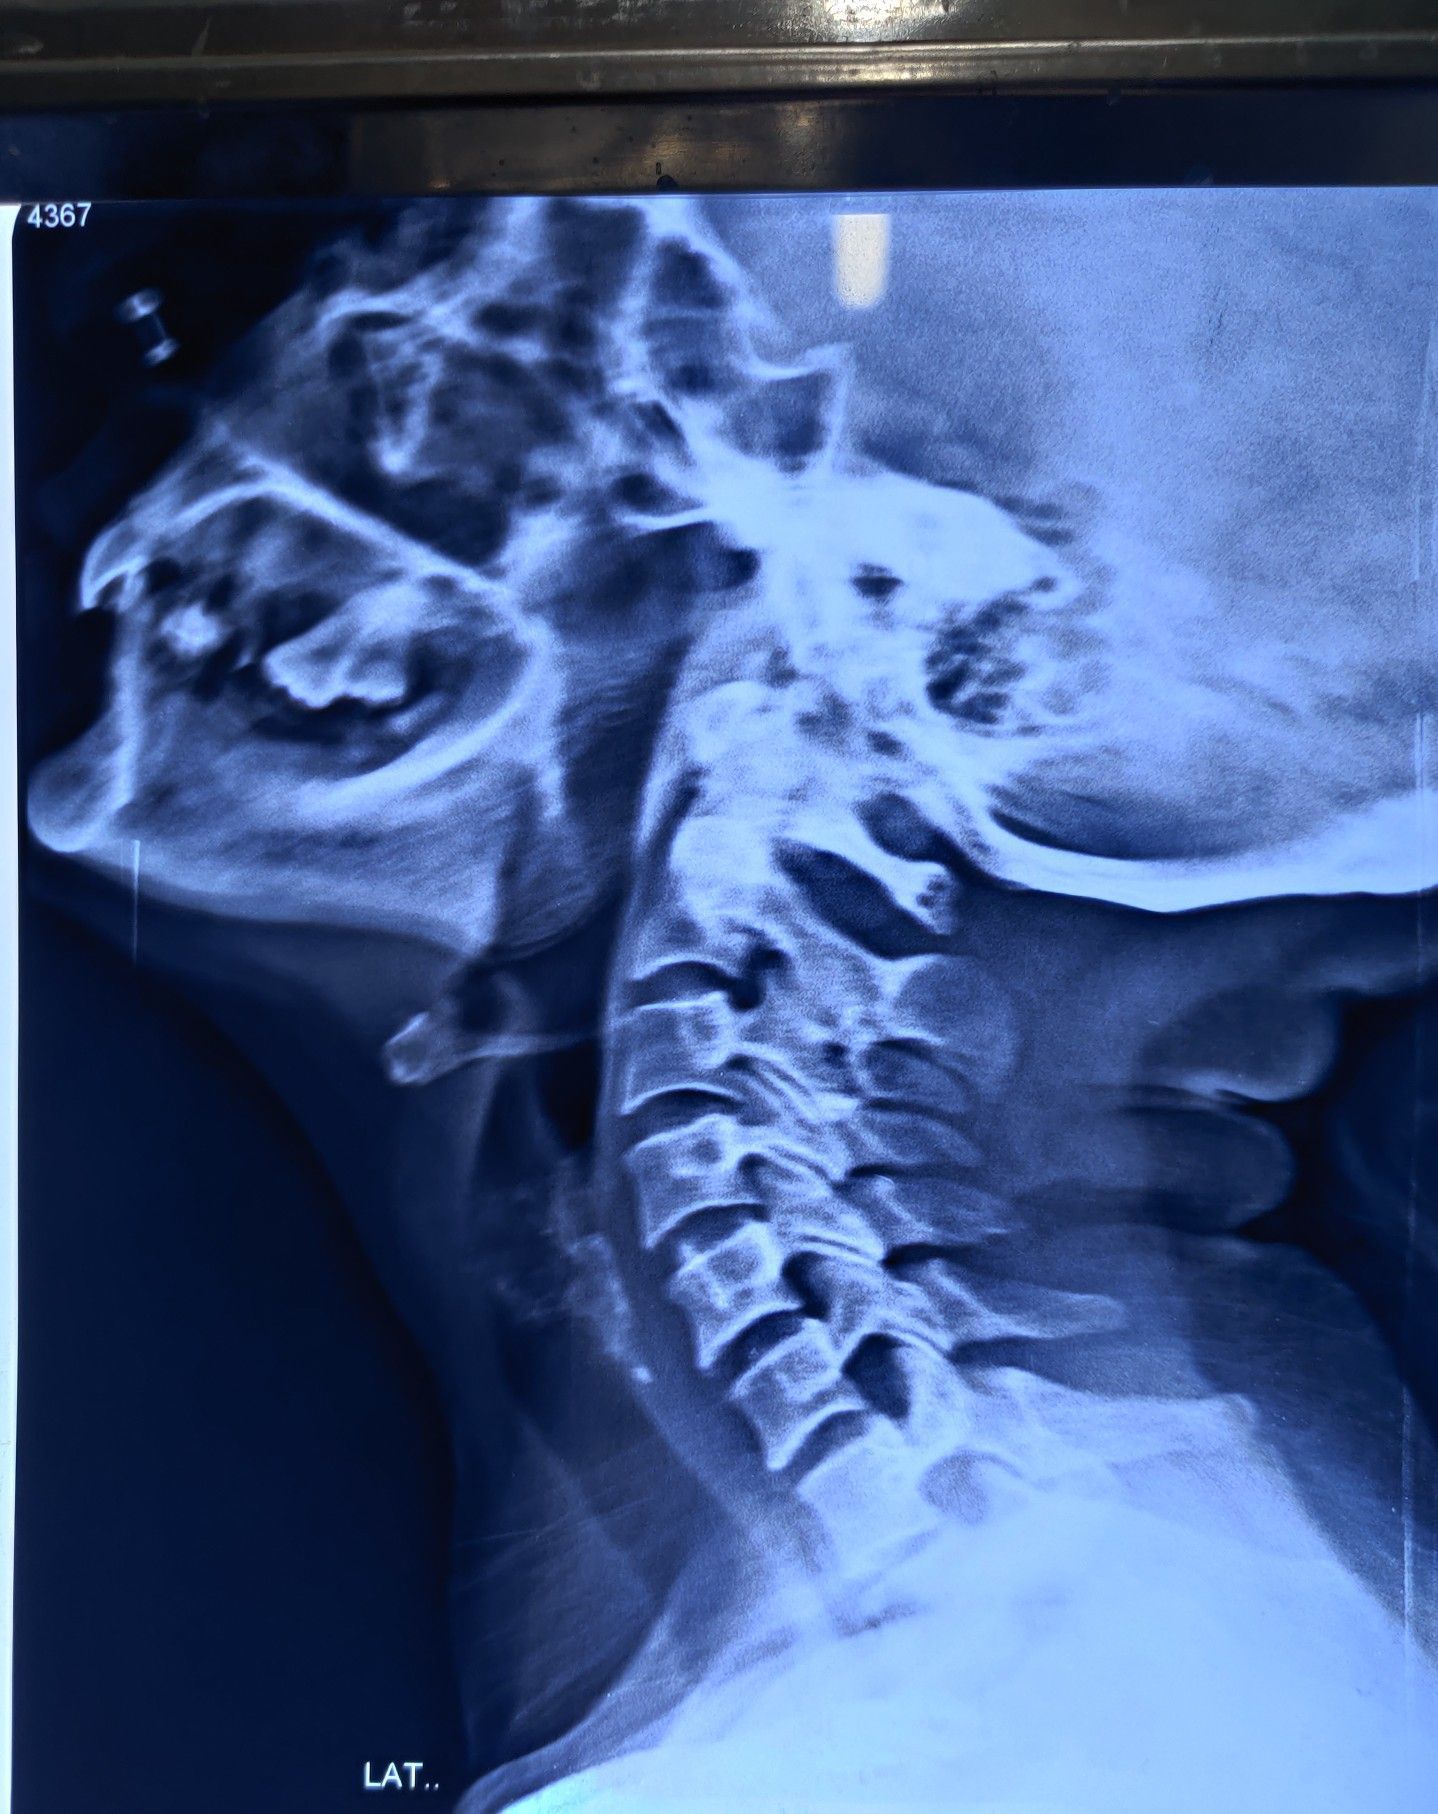

Can you the diagnosis?

Pt complaining of esophageal dysphagia

Xray

Er

Thraot